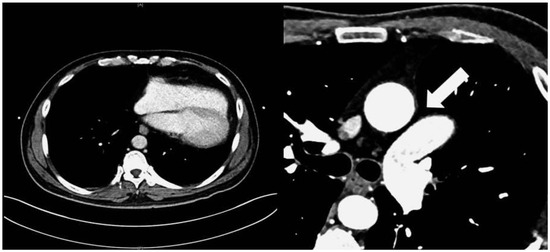

An Unusual Cause of Thromboembolic Disease

by Marc L. Fischer, Peter Matt, Beat A. Kaufmann and Arnheid Kessel-Schaefer

Cardiovasc. Med. 2015, 18(7-8), 229; https://doi.org/10.4414/cvm.2015.00348 - 12 Aug 2015

Cited by 1 | Viewed by 160

Abstract

The most frequent noncardiac sources of systemic embolism are mural thrombi within proximal aneurysms, ulcerated atherosclerotic plaques, and paradoxical emboli originating from the venous side of the circulation [...] Full article